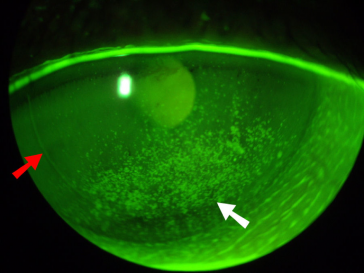

اختم تغريداتي بصورة توضح مايراه #طبيب_العيون في عين المريض الذي يعاني من جفاف متوسط او شديد.

مع تمنياتي لكم بصحة وافرة